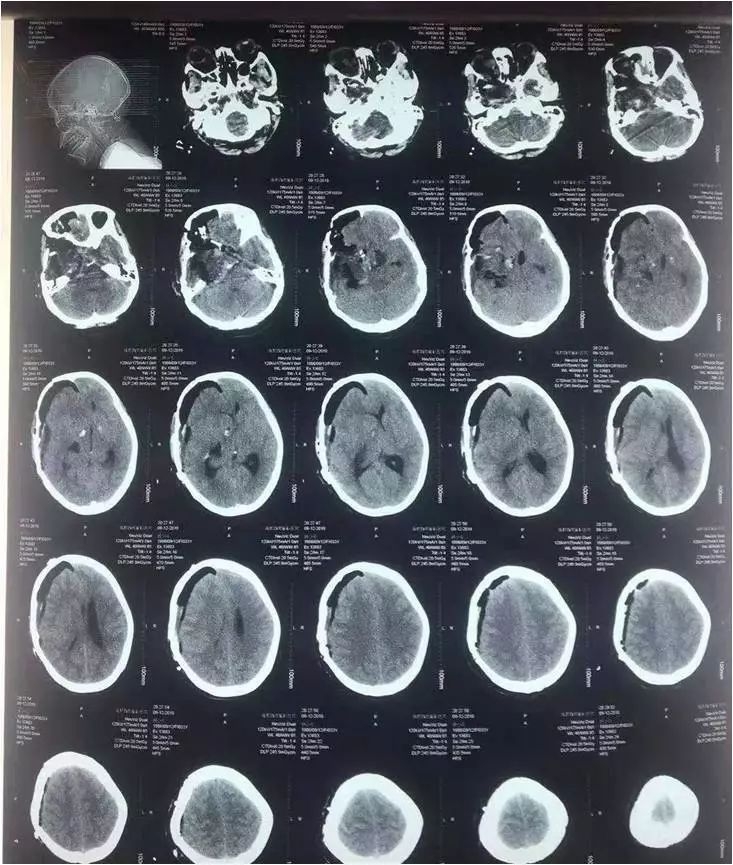

中脑海绵状血管瘤手术

术前

术后

颅眶沟通性肿瘤切除手术

术前

术后(肿瘤全切)